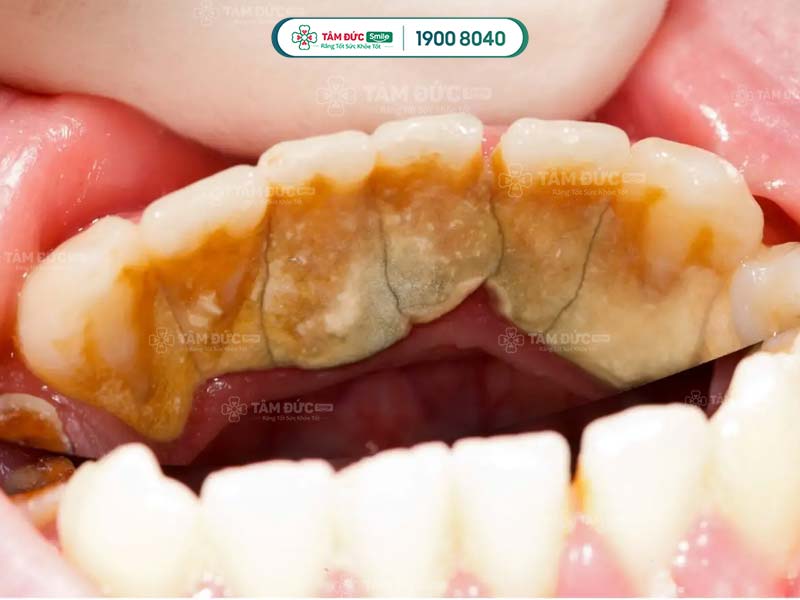

- Phát hiện có nhiều cao răng và mảng bám ở thân răng hoặc dưới nướu.

Cao răng không phải là nguyên nhân trực tiếp gây ra các bệnh lý về răng miệng, nhưng lại là nơi trú ngụ của nhiều loại hại khuẩn. Vì vậy, cao răng tạo điều kiện để vi khuẩn gây bệnh.

Cao răng tích tụ lâu ngày sẽ gây ra các bệnh lý như: Sâu răng, viêm nướu, tụt nướu, mòn men răng, viêm nha chu,... Do đó, cạo cao răng thường xuyên giúp Quý khách ngăn chặn vi khuẩn phát triển, giảm nguy cơ mắc phải các bệnh lý răng miệng.

Cao răng có màu sẫm, tích tụ trên thân răng làm ảnh hưởng đến thẩm mỹ nụ cười. Cạo cao răng giúp Quý khách loại bỏ các mảng bám tối màu, trả lại hàm răng trắng sáng và đẹp mắt hơn.

Vi khuẩn tích tụ trong cao răng thời gian dài sẽ tấn công vào sâu bên trong, làm hư hại răng và nướu nặng nề. Lâu dần, xương hàm của Quý khách có thể bị tiêu biến, tăng nguy cơ lung lay răng vĩnh viễn. Như vậy, cao răng nghiêm trọng có thể làm cho Quý khách đối mặt với vấn đề mất nhiều răng cùng lúc.